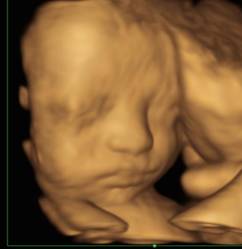

你们医院有四维彩超吗?有!相约与宝宝第一次”见面“

相信准妈妈们都很好奇,自己的宝宝在肚子里发育得如何了?长得又像谁呢?为了让孕妈妈与宝宝享受更全面优质的服务,瑞安市人民医院开展系统(四维)超声,为宝宝留下第一份照片和小视频!那么四维超声是什么呢?今天我们就来聊一聊什么是四维超声,它和二维、三维超声有什么区别,在检查过程中我们又该注意些什么呢?

三维超声:在二维超声的基础上通过三维重建技术给宝宝拍的照片,需要宝宝保持相对静止的状态。

四维超声:即实时动态三维超声成像,能够直观地观察到宝宝在肚子里的活动情况。

并非如此。如图所示,有些宝宝在进行超声检查时,会用手挡脸,此时宝宝的面部就无法清晰显示,这时候检查医生就需要您出去走走,喝喝水,吃吃东西,多动动,让肚子里的宝宝也动一动,才能继续进行检查。有些调皮的宝宝说不定需要您多走上几次,但为了仔细检查宝宝的情况,这些等待都是值得的。